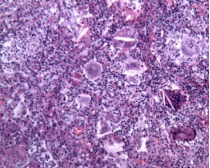

外科肺活检,肺组织病理提示巨细胞性间质性肺炎(GIP)。

ero为什么不显示叶俏教授:HRCT是发现和鉴别「过敏性肺炎」的重要环节,何种表现指向预后不良?使患者发病的危害因素躲在哪些环境中?_https://www.jmylbn.com_新闻资讯_第49张

肺组织病理中,非纤维化型HP包括细胞性间质性肺炎(可见细支气管中心性分布,细胞性NSIP型,以淋巴细胞为著)、细胞性细支气管炎、未形成非坏死性肉芽肿(与结节病的肉芽肿呈显著差别)。纤维化型HP包括慢性纤维化性间质性肺炎(结构扭曲、成纤维细胞灶±胸膜下蜂窝肺纤维化性NSIP型)、气道中心性纤维化。

比如细胞性细支气管炎(下图左),可以看到很多淋巴细胞浸润;还有非坏死性肉芽肿炎(下图中),肉芽肿的边界并不清楚,有一些内上皮细胞和炎症浸润;细胞性慢性间质性肺炎——「NSIP样改变」(下图右)。